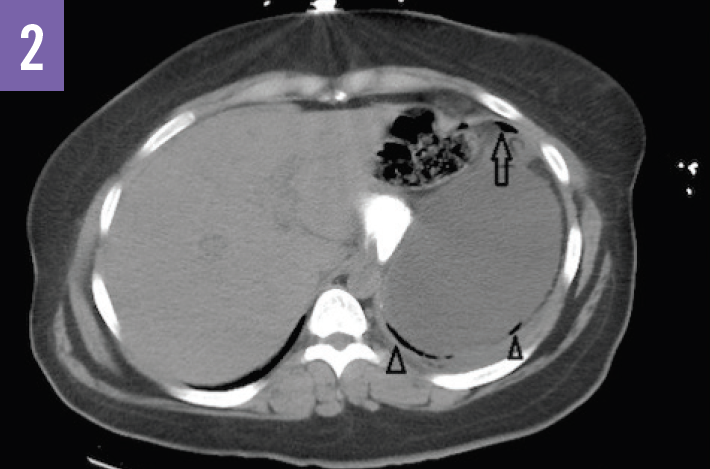

Diagnostic tests. An acute abdominal radiograph series was unremarkable for pneumoperitoneum but demonstrated a gastric air bubble (Figure 1). Computed tomography (CT) of the abdomen and pelvis with oral diatrizoate meglumine and diatrizoate sodium solution contrast medium demonstrated free air under the left hemidiaphragm and gastric pneumatosis (Figure 2), possible obstructions of the bilioenteric limb and within the common channel (Figures 3 and 4), and fat stranding at the pancreatic head (Figure 5).

Based on the imaging results, the patient received a diagnosis of internal hernia with perforation of the gastric remnant.